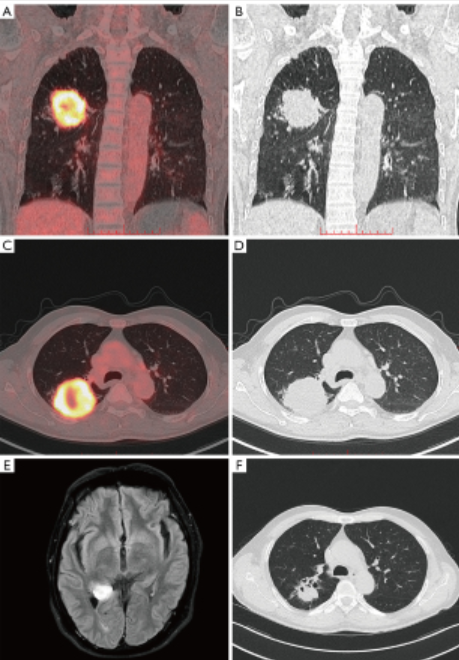

病史摘要:60余岁男性患者,有冠状动脉钙化和良性前列腺增生病史。2024年中期常规体检发现肝占位性病变,无腹痛、体重下降、呼吸功能障碍等症状。 诊疗过程:胸部CT发现右肺上叶孤立性毛刺状结节,腹部MRI提示肝病灶可能为肝细胞癌,PET-CT显示多处高代谢活性。肿瘤标志物CEA显著升高。行肝段切除术,病理提示肺来源转移性神经内分泌癌;后行右肺上叶部分切除术,确诊原发性肺大细胞神经内分泌癌伴脏